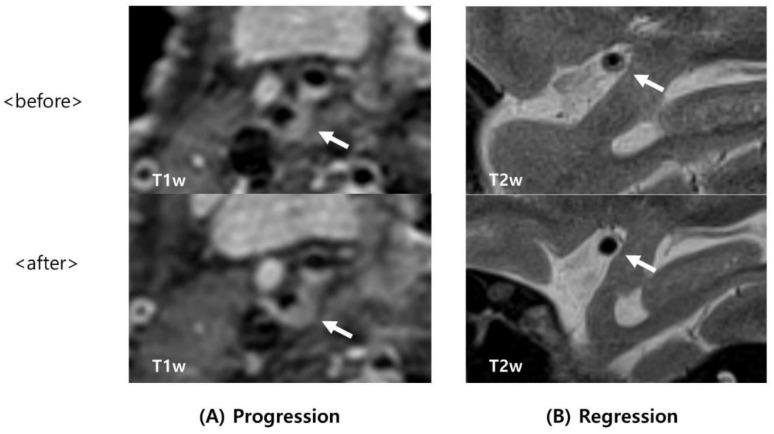

Atherosclerosis can affect multiple arteries, and result in stroke and heart disease. Clinical and conventional imaging is insufficient to predict the progression of atherosclerosis. This study investigates risk factors that rely on high-resolution magnetic resonance imaging (HR-MRI). Patients with cerebral artery stenosis who had undergone HR-MRI at least twice were included. The demographics, risk factors, and proportion of patients with cerebral artery stenosis were investigated. The association between atherosclerotic plaque characteristics and the progression or regression of artery stenosis was also analyzed. A total of 42 patients were analyzed, with a median follow-up of 16.88 ± 12.53 months. The mean age of all subjects was 63.1 ± 9.15 years, and 83.3% of them were male. The incidences of stenosis of the basilar, proximal internal carotid, and middle cerebral arteries were 21.4%, 61.9%, and 16.7%, respectively. Intraplaque hemorrhage (IPH) was detected in 20 (47.6%) patients. Multivariate analysis showed that age (odds ratio (OR), 0.87; = 0.014), smoking (OR, 0.11; = 0.033), and IPH regression (OR, 10.13; = 0.027) were associated with stenosis regression. The progression of IPH (OR, 115.80; = 0.007) was associated with stenosis progression. Results suggest that IPH on HR-MRI is associated with changes in cerebral atherosclerotic stenosis.